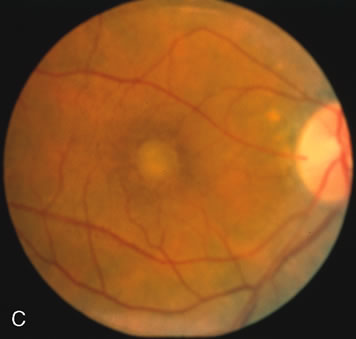

Of more clinical importance is the role of FA in the diagnosis and treatment of cystoid macular edema (CME) (Fig. 1C and D). Stereoscopic FA indicates that the leakage, which may be diffuse or have the typical petaloid stellate appearance of CME, can come from the perifoveal retinal capillaries, from the choroid through the RPE, or from a combination of both sources.4 With the recent suggestion that CME in RP may be successfully treated with acetazolamide,5, 6 FA is thus important to document the diagnosis of CME, establish the origin(s) of leakage, and follow patients during and after therapy.